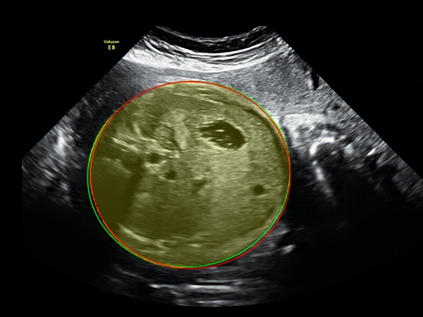

In this paper, we propose an end-to-end multi-task neural network called FetalNet with an attention mechanism and stacked module for spatio-temporal fetal ultrasound scan video analysis. Fetal biometric measurement is a standard examination during pregnancy used for the fetus growth monitoring and estimation of gestational age and fetal weight. The main goal in fetal ultrasound scan video analysis is to find proper standard planes to measure the fetal head, abdomen and femur. Due to natural high speckle noise and shadows in ultrasound data, medical expertise and sonographic experience are required to find the appropriate acquisition plane and perform accurate measurements of the fetus. In addition, existing computer-aided methods for fetal US biometric measurement address only one single image frame without considering temporal features. To address these shortcomings, we propose an end-to-end multi-task neural network for spatio-temporal ultrasound scan video analysis to simultaneously localize, classify and measure the fetal body parts. We propose a new encoder-decoder segmentation architecture that incorporates a classification branch. Additionally, we employ an attention mechanism with a stacked module to learn salient maps to suppress irrelevant US regions and efficient scan plane localization. We trained on the fetal ultrasound video comes from routine examinations of 700 different patients. Our method called FetalNet outperforms existing state-of-the-art methods in both classification and segmentation in fetal ultrasound video recordings.